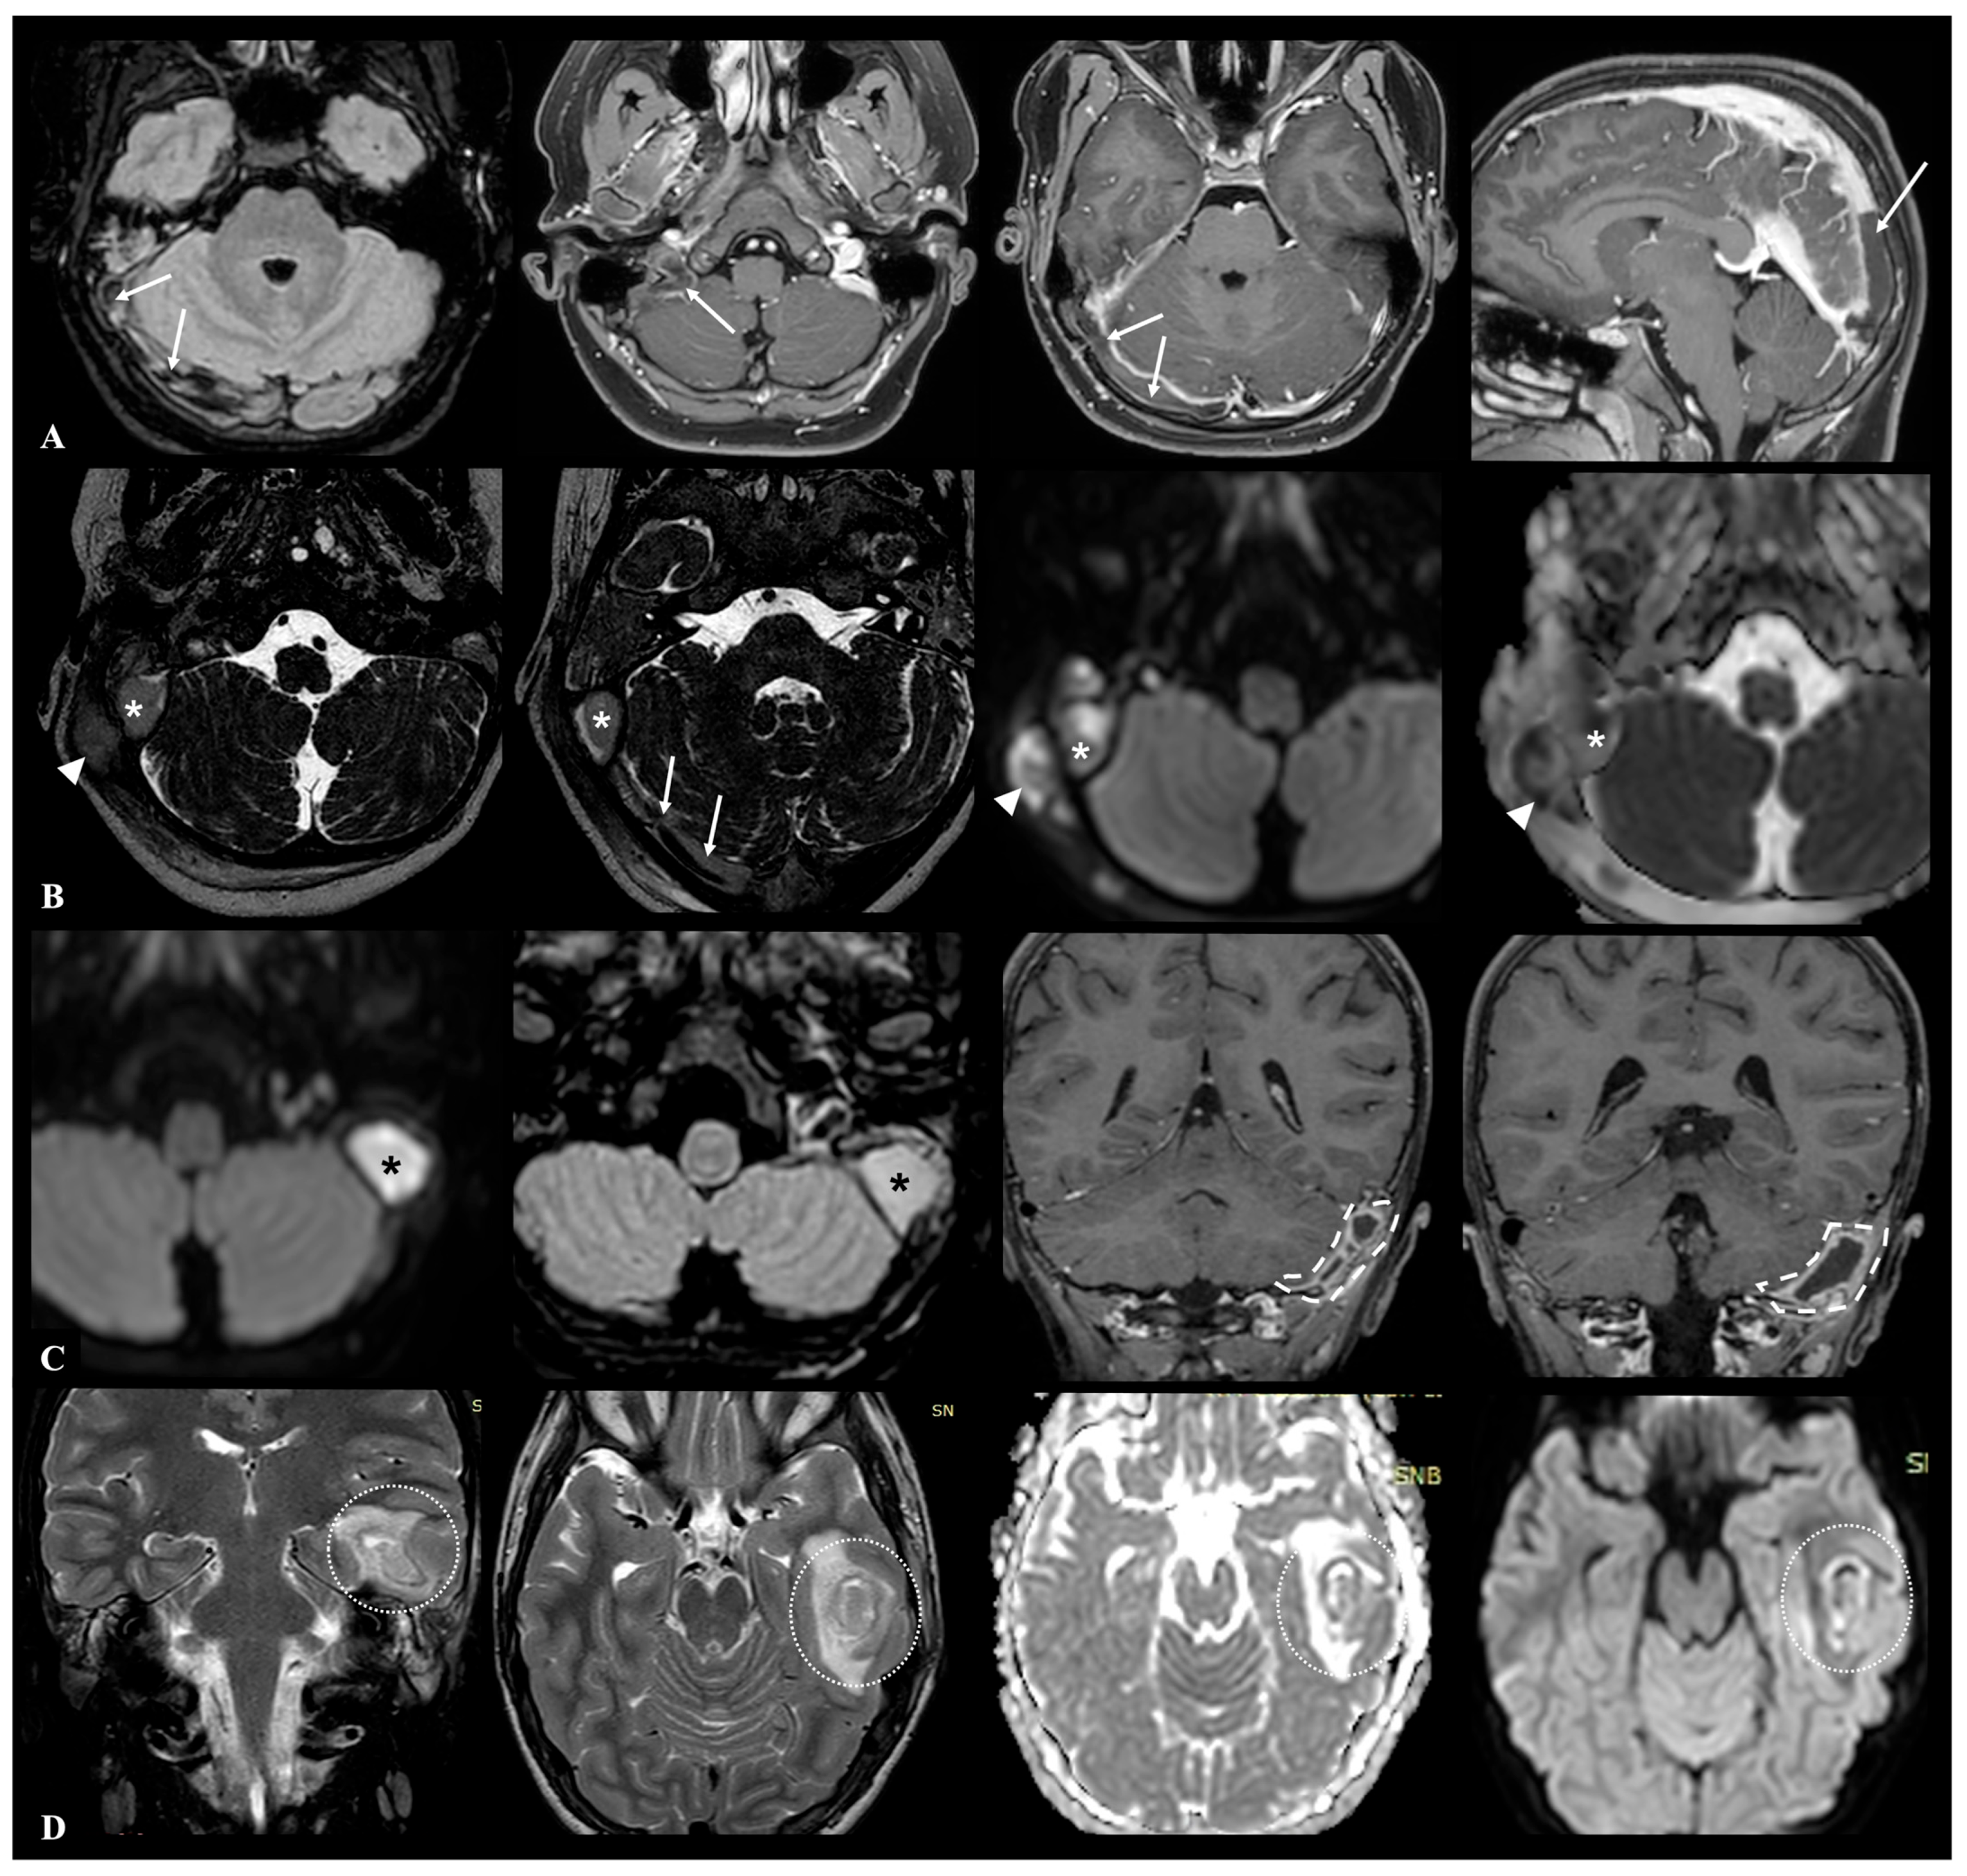

All neuroradiological images were re-evaluated in consensus by two experienced neuroradiologists to identify normal anatomical variants potentially considered predisposing or facilitating the intracranial spread of infection from the otomastoid region. Specifically, these factors were classified as follows: (1) vascular variants involving course, or position of the sigmoid–jugular sinus complex and/or the presence of aberrant mastoid emissary veins (defined as a transosseous connection between the sigmoid dural venous sinus and the suboccipital venous plexus); (2) variants in the thickness of the tegmen tympani; and (3) pneumatization variants, including hyperpneumatization of mastoid air cell compartments and/or the presence of accessory air cells in retroauricular or perilabyrinthine locations. Cases in which inflammatory bone destruction obscured or mimicked normal anatomical variants were carefully reviewed in consensus by two experienced neuroradiologists, and when diagnostic uncertainty persisted, they were excluded from morphometric analysis. An example of the considered anatomical variants is shown in Figure 2.

Figure 2. Example of normal mastoid anatomical variants observed on the left side in a same 11-year-old male control patient undergone brain CT examination due to traffic injury: (A) grade IV mastoid hyperpneumatization according to Han et al., with air cells extending beyond the sigmoid sinus posteriorly (dashed lines); (B) thinned tegmen tympani (white arrow); (C,D) accessory mastoid emissary vein enlargement (dotted lines); (E,F) high riding jugular bulb type 4 according to Manjila et al. classification (star), located above the inferior margin of the posterior semicircular canal (white circle), with dehiscent sigmoid plate protruding into middle ear (white arrowhead).